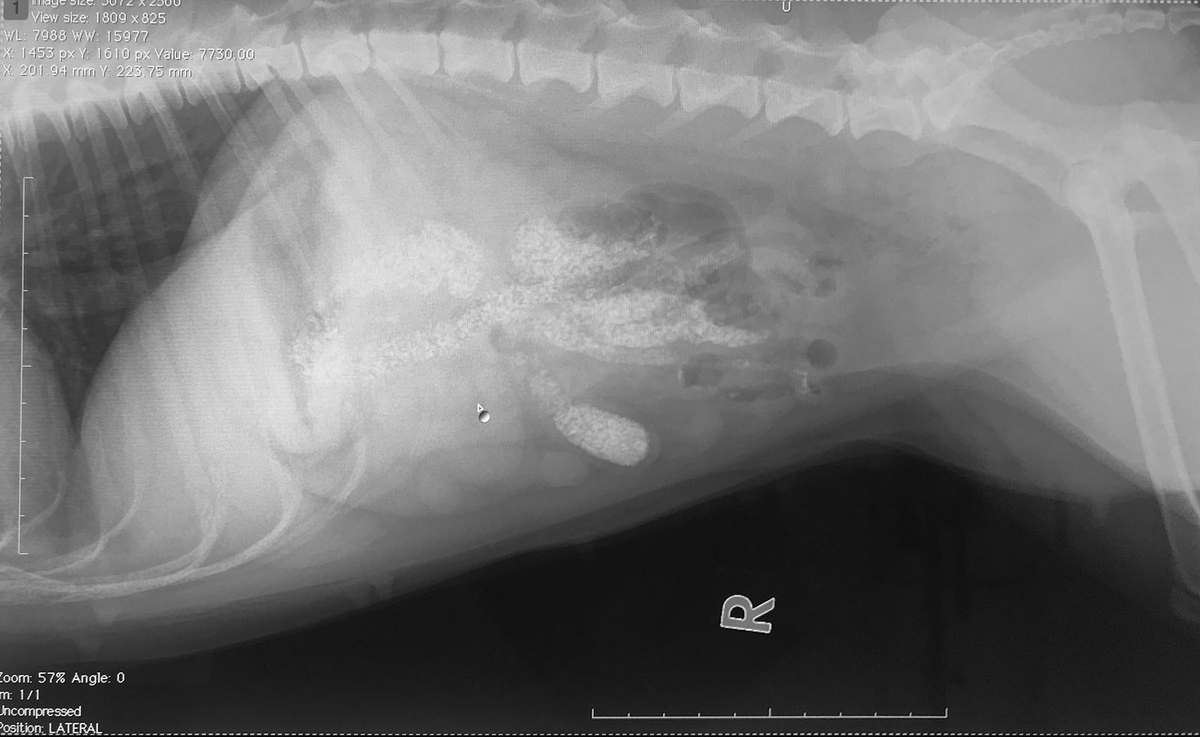

何かあったのかと思い、ドキドキして話を聞くと「最近砂をたべていませんか?」とのこと。レントゲンにびっしり大量の砂が写っているというのです。

慌てて病院にいくと、確かに腸には砂が一杯です。

レントゲンは平面的に撮影をするので、少量の砂が満遍なくウンチに混じっていると、びっしりのように映ってしまいます。

今回はそれが起きているのだと思われました。

レントゲンの様子からして、腸がすぐに閉塞するような状態ではないものの、もしも手術の後で閉塞すると危険な状態になるということで、念のために手術を1週間延期して、排泄されるかどうか様子を見るという事に。決心の手術だったのに、気を削がれてしまいました。

聞けばレントゲンで、腸に砂が大量に詰まっているとのこと。

画像を見せてもらうと「本当だ!」

しかしこれ、大量ではなく、ボール遊びの時に飲み込んだ砂が、満遍なくウンチに混じっただけの模様。